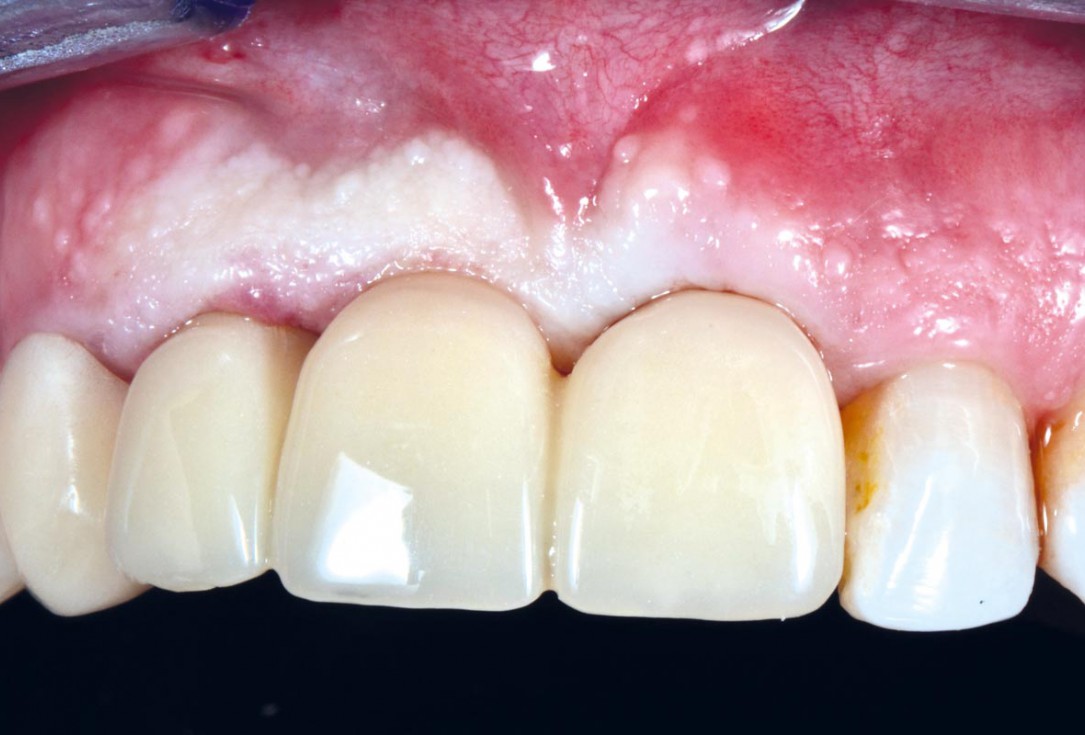

17/17 - Final prosthetic restoration.

Socket preservation using cerabone® and Straumann® Emdogain® - Dr. S. Pelekanos